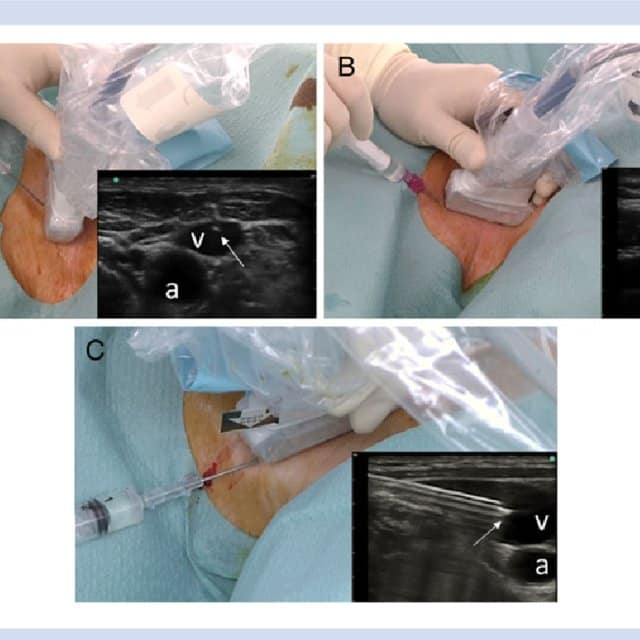

Лікування дітей в умовах відділення інтенсивної терапії вимагає проведення багатьох інвазивних процедур. Наприклад, постановка центральних та периферичних венозних катетерів, провідникова анестезія. Раніше такі маніпуляції були пов'язані з високим ризиком ускладнень, бо проводились "в сліпу" по анатомічним орієнтирам. Метод УЗД, який сьогодні став більш доступним, дозволяє проводити ці інтервенції з візуалізацією. Тобто лікар бачить положення голки в глибині тканин, що спрощує процедуру та значно знижує ризик розвитку ускладнень. Крім того УЗД дозволяє швидко оцінити хворого з травмою грудної клітки та органів черевної порожнини і необхідність термінового оперативного лікування.